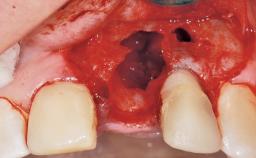

A 33-year-old female patient presented with an upper left central incisor that required extraction after a failed endodontic therapy. The tooth had been traumatized when the patient was a teenager and had undergone several endodontic treatments, including two apicectomy procedures. The patient was in good health and did not smoke. Clinical examination showed that the patient had a high lip line. In full smile, the gingival margins of the upper teeth were visible to the first molars. The gingival margins of central incisors 11 and 21 were only just showing. Examination of tooth 21 confirmed that the tooth was mobile and had hypererupted by 1 mm.

Socket Integrity Damage to one or more bone walls

Bone Volume Damage to one or more socket walls

Bone Augmentation Horizontal|Simultaneous

Augmentation Materials Xenogenous|Membrane

Soft Tissue Grafting Simultaneous